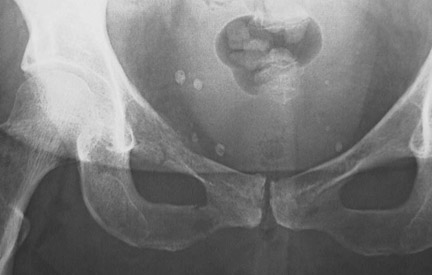

Image 3.2

A radiograph of the pelvis reveals a

fracture

.